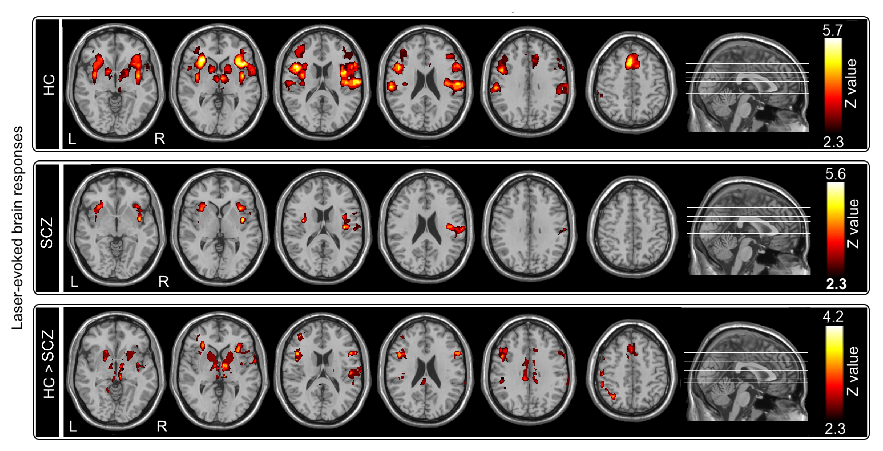

(1)与健康人群相比,精神分裂症患者对疼痛刺激不敏感,表现为患者对疼痛的主观强度评分较低、激光疼痛诱发电位各成分振幅较低和潜伏期较长(图1)、激光疼痛诱发BOLD脑响应较低(图2)。

图 2 精神分裂症患者与健康人群在疼痛刺激诱发的BOLD脑响应差异